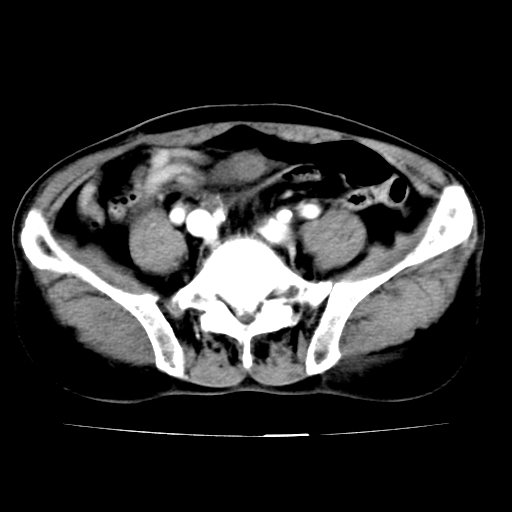

男,75岁,腹痛月余,彩超发现脐周腹主动脉异常回声。临床诊断:腹主动脉瘤。

ct诊断:右骼总动脉囊性动脉瘤并瘤内附壁血栓形成,与下腔静脉之间形成动静脉瘘。

请问各位老师:能排除动脉瘤破裂的可能吗?

各位老师注意到下腔静脉的充盈缺损了吗?注意到动静脉漏了吗?

当时是扫描的标准动脉期,可是下腔静脉与腹主动脉同步强化且幅度一致。所以我想动静脉瘘是存在的。